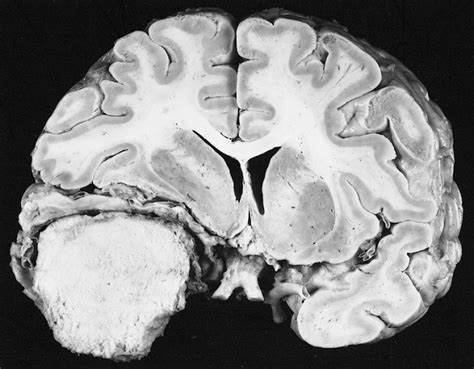

脑膜瘤 是由覆盖大脑和脊髓的膜层产生的肿瘤,而不是脑组织本身产生的肿瘤。大脑凸面脑膜瘤是指起源于大脑凸面的脑膜瘤,其发病率仅次于矢状窦旁脑...

脑膜瘤是较常见的原发性脑瘤,占全部新诊断的原发性脑瘤的近三分之一。脑膜瘤被认为是由蛛网膜帽细胞衍生而来,并位于硬膜(颅内外实质)。脑...

脑膜瘤属于良性肿瘤,生长慢,病程长。因肿瘤呈膨胀性生长,病人往往以头疼和癫痫为首发症状。根据肿瘤位置不同,还可以出现视力、视野、嗅觉或听...